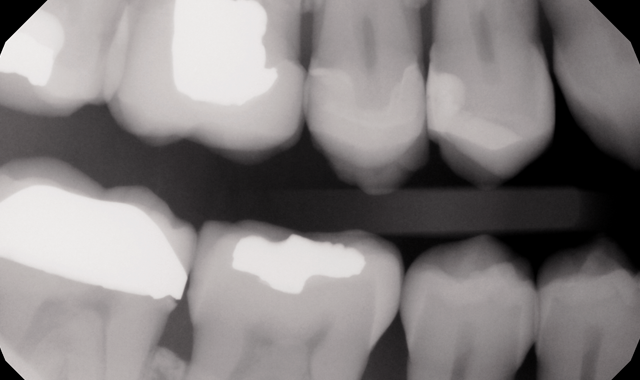

The patient agreed to intraoral digital bitewings in 2013. The scope of this X-ray is limited, as is their size and thickness. At the time these X-rays were taken they provided no diagnostic information about the wisdom teeth. Recalling this patient’s radiophobia, the possibility of doing retakes was not pleasant.

Image of digital intraoral bitewings